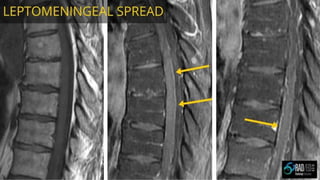

CNS RADIOLOGY FOR RADIATION ONCOLOGISTS